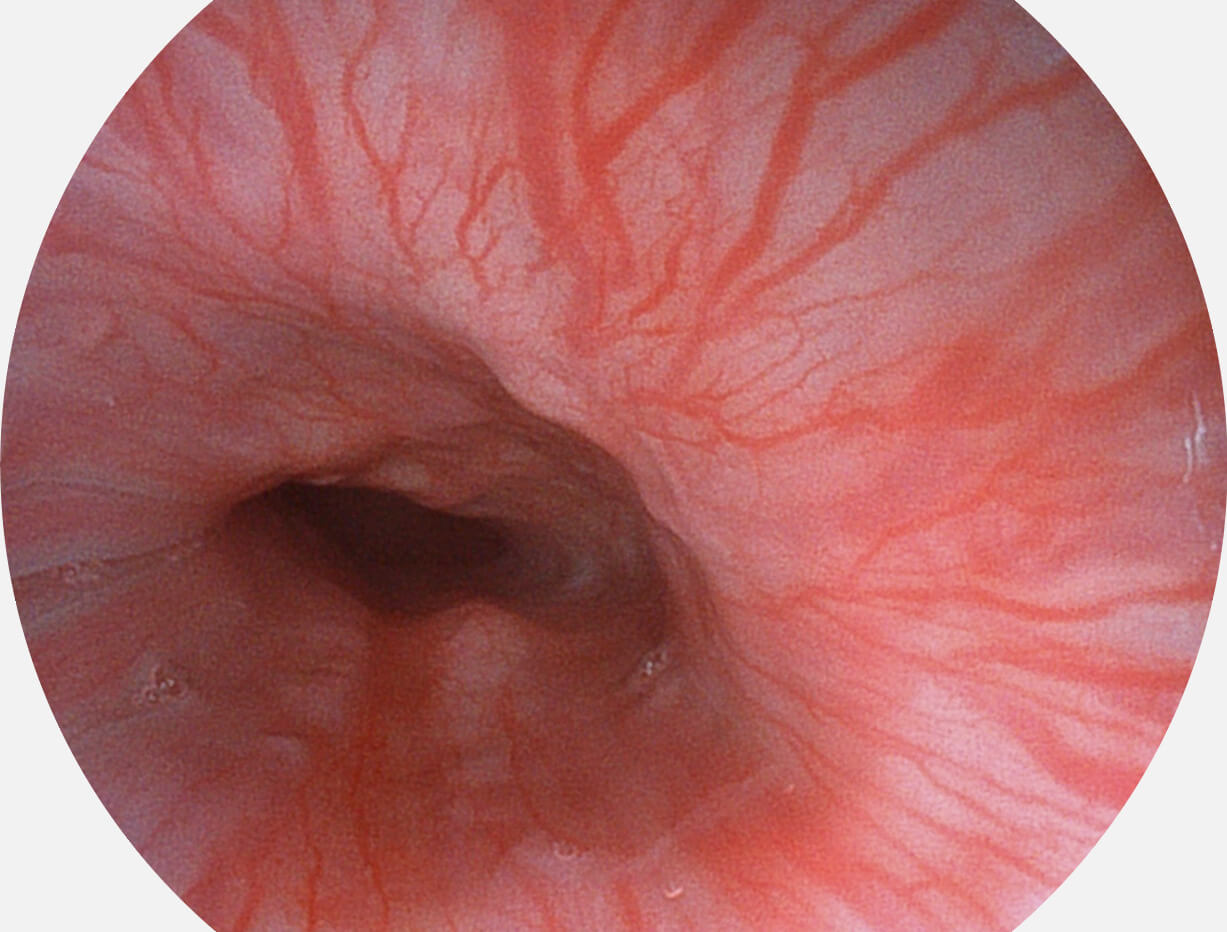

SFI图像

白光图像